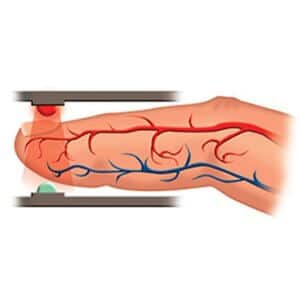

- Easy to Use Illustrated finger guide ensures easy and accurate placement by caregiver or patient

- Tear Resistant Increases the number of times the sensor can be repositioned

- Available in a Variety of Sizes With sizes from neonate to adult you can ensure a proper fit for a reliable reading